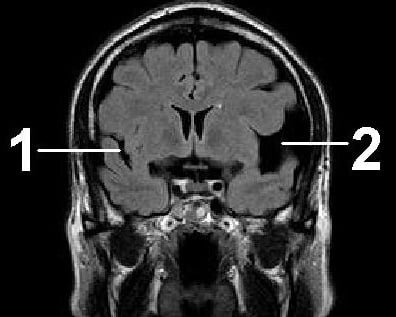

- томографии (компьютерной или магнитно-резонансной) головного мозга (расширение субарахноидального пространства, желудочков и цистерн мозга, иногда кисты в подоболочечном пространстве, спаечный и атрофический процессы при отсутствии очаговых изменений в веществе мозга);

Как МРТ покажет арахноидит головного мозга?

Слипчивый арахноидит характеризуется слипанием нервных корешков и спинного мозга, которые могут выглядеть как слипшиеся пучки на МРТ-снимках. Этот признак лучше всего виден на Т2-взвешенных изображениях. Повышенный сигнал от окружающих тканей на Т2-взвешенных изображениях указывает на отек и воспаление.